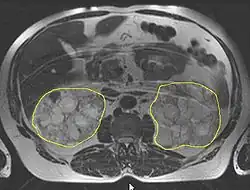

Die Diagnose wird in der Regel durch eine Sonografie („Ultraschall“)[14] oder durch andere bildgebende Verfahren, wie beispielsweise die Magnetresonanztomografie, gestellt.[15] Mit der Sonografie können mit modernen Geräten Zysten bis herab zu einer Größe von 5 mm diagnostiziert werden. Die Früherkennungsrate bei 20-jährigen Patienten liegt bei etwa 90 %.[16] Die Computertomografie bietet zwar eine höhere Auflösung mit besserer Bildqualität, sie wird jedoch vor allem wegen der Strahlenbelastung nicht für Patienten-Screenings, sondern nur bei speziellen diagnostischen Fragestellungen eingesetzt.[3]

Die Entstehung und Entwicklung von Zystennieren, die Pathogenese, beruht auf einer zystischen Degeneration der sogenannten Nierenkanälchen (Tubuli, auch: Harnkanälchen) in den Nieren. Diese führt bei der autosomal-dominant vererbten PKD im Verlauf von Jahrzehnten zu einer zunehmenden Vergrößerung der Nieren. Es kann dabei zu einer Funktionseinschränkung bis hin zum völligen Verlust der filtrativen Nierenfunktion kommen. Beide Nieren sind gleichmäßig betroffen. Mehrere hundert Zysten, die in ihrer Erscheinung prall elastisch sind, können dabei pro Organ ausgebildet werden. Masse und Volumen der Nieren können dadurch erheblich anwachsen. Während eine gesunde Niere durchschnittlich eine Masse von 160 g aufweist, können polyzystische Nieren bis zu 8 kg bei bis zu 40×25×20 cm³ (= 20 Liter) Volumen erreichen (gesunde Niere: 12×6×3 cm³ = 0,216 Liter). Trotz des erheblich gesteigerten Platzbedarfs des Organs kommt es nur relativ selten zu Funktionsstörungen der benachbarten Organe.[24]

Die Zysten finden sich sowohl am Nierenmark (Medulla renis) als auch an der Nierenrinde (Cortex renalis). Prinzipiell kann dabei jeder Bereich eines Nephrons eine Zyste ausbilden. Bevorzugt betroffen sind jedoch die Glomeruli und die Henlesche Schleife. Gefüllt sind die Zysten mit dem sogenannten Tubulusharn. Der Durchmesser einer einzelnen Zyste kann von wenigen Millimetern bis über 100 mm sehr stark variieren. Große Zysten können so mehrere hundert Milliliter Tubulusharn enthalten. Das Innere der Zysten besteht aus einem einschichtigen Plattenepithel oder einschichtigem isoprismatischen (kubischen) Epithel. Mit dem Fortschreiten der Erkrankung können sowohl die Anzahl als auch die Größe der vorhandenen Zysten zunehmen.[3]

Das Durchschnittsalter bei Diagnosestellung der ADPKD liegt derzeit bei 27 Jahren. Wenn eine Nierenfunktionseinschränkung eintritt, kommt es zu einer raschen Abnahme der GFR von ≈5,9 ml/min pro Jahr. Bislang war keine randomisierte Studie in diesem späten Stadium der Erkrankung in der Lage, den günstigen Effekt einer Behandlung nachzuweisen. Wegen der langen präsymptomatischen Phase und des späten Auftretens der Niereninsuffizienz sind die primären Endpunkte, welche üblicherweise bei Studien zu chronischen Nierenerkrankungen untersucht werden, wie Zeit bis zur Dialysebehandlung, Verdoppelung des Serum-Kreatinins oder Tod, bei Studien zu polyzystischen Nierenerkrankungen nur bedingt brauchbar.[94] Aus diesem Grund wurde das Consortium for Radiologic Imaging Studies of Polycystic Kidney Disease. (CRISP) gegründet, dessen Aufgabe es ist, bildgebende Verfahren zu untersuchen, die in den Frühstadien Aussagen zum Erkrankungsverlauf ermöglichen. Ein wichtiges Ergebnis der Untersuchungen von CRISP mittels Magnetresonanztomographie ist, dass bei Patienten mit ACPKD die Zysten kontinuierlich und quantifizierbar wachsen und dass das Zystenwachstum mit der Abnahme der Nierenfunktion korreliert. Das heißt, eine stärkere Zunahme der Zystengröße ist mit einer schnelleren Abnahme der Nierenfunktion assoziiert.[95]